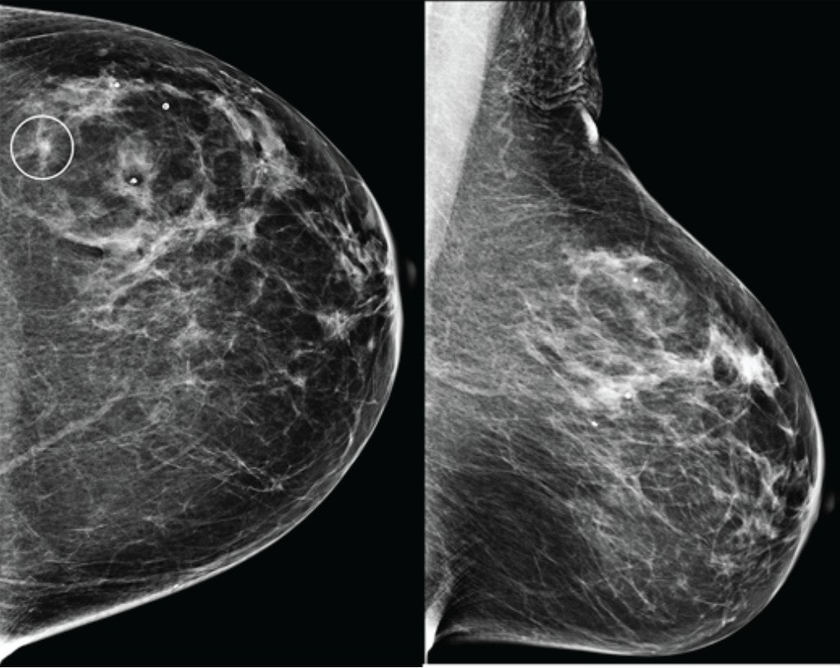

В конце августа 2025 года американский стартап Calidar представил инновационную систему 4D-маммографии, которая выводит точность диагностики злокачественных образований молочной железы на новый уровень. Эта платформа визуализации использует рентгеновскую дифракцию и искусственный интеллект для проведения исследования на молекулярном уровне.

Первая в своем роде система 4D-маммографии, разработанная компанией Calidar, позволяет решить существующие проблемы. Устройство измеряет, как рентгеновские лучи рассеиваются на молекулярном уровне: данный процесс известен как рентгеновская дифракция. Это создает уникальную структурную сигнатуру, которая отражает внутренний состав ткани молочной железы.Российский рынок WMS-систем: оценки, тренды и крупнейшие поставщики. Обзор TAdviser

В отличие от традиционных рентгеновских снимков, которые основаны на форме и плотности, рентгеновская дифракция предоставляет дополнительную диагностическую информацию о том, из чего состоит ткань. Эти специфичные данные позволяют классифицировать раковые и доброкачественные образования с точностью, в четыре раза превышающей показатели традиционных систем визуализации.[1]